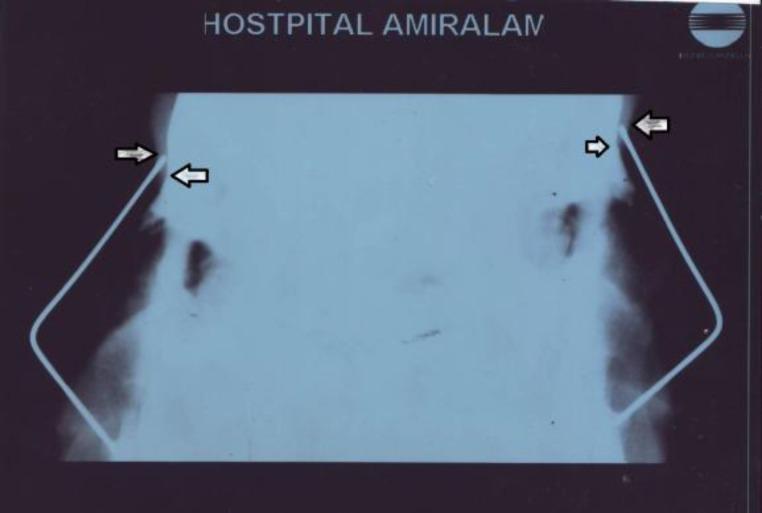

In this study, a single structure in the form of L-strut was attempted to be created by using one 0.035" Kirschner wire and an autologous costal graft out of the 10th and 11th ribs. This study involved 13 cases, most of whom were traumatic. The corrective surgical techniques used in this study will be described in detail.

在本研究中,尝试用一根0.035英寸的克氏针和取自第10和第11肋的自体肋软骨移植物构建一个L形支柱单一结构。本研究纳入13例患者,多数为外伤所致。本研究中使用的矫正手术技术将予以详细描述。